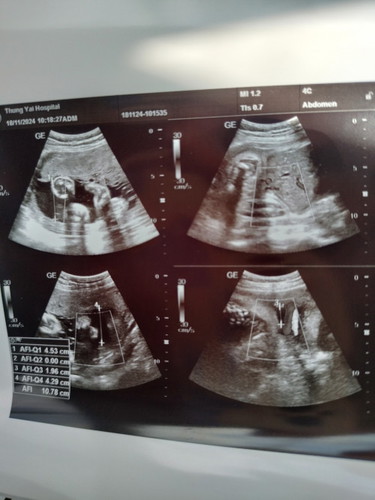

แบบนี้ เพศอะไรคะแม่ๆ

ผู้หญิงไหมคะ ไม่มีอะไรเด่ๆมา คุณหมอบอกว่าไงคะ

เพศหญิงค่ะ